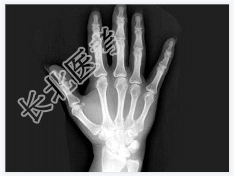

- [材料题] 女,41岁,纺织工,腕部疼痛无力数周。

- 简答题1、结合CR和MR,最可能的诊断是?

- 简答题2、右侧月骨缺血坏死的常见原因是什么?

- 简答题3、右侧月骨缺血坏死的早期症状有哪些?

- 简答题4、右侧月骨缺血坏死的治疗方案有哪些?